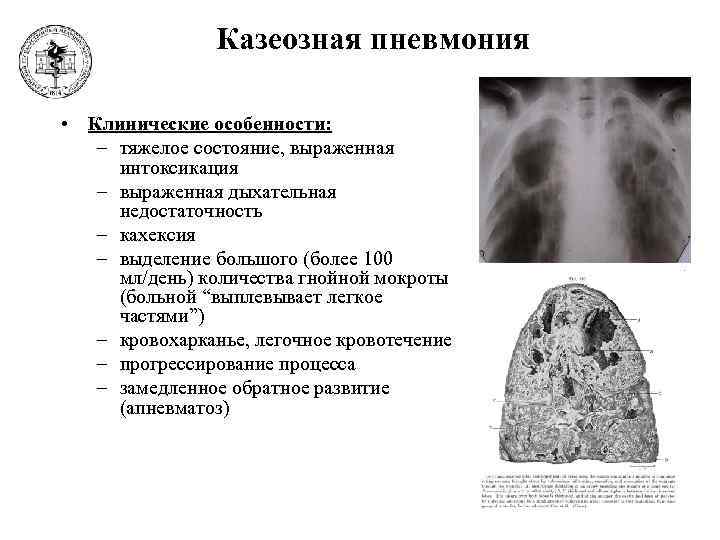

Симптомы и признаки туберкулеза: как распознать заболевание

Раздел: Визуальные уроки